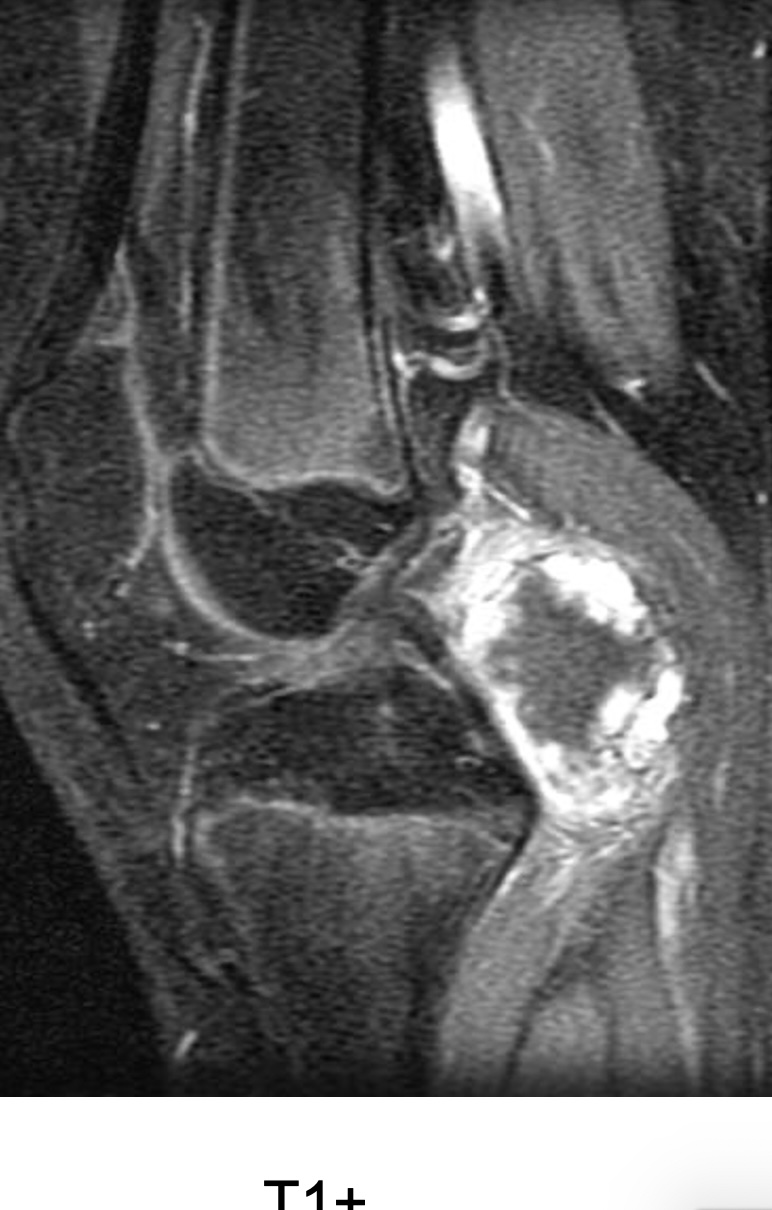

Figure 1 for case Synovial chondromatosis

Figure 1